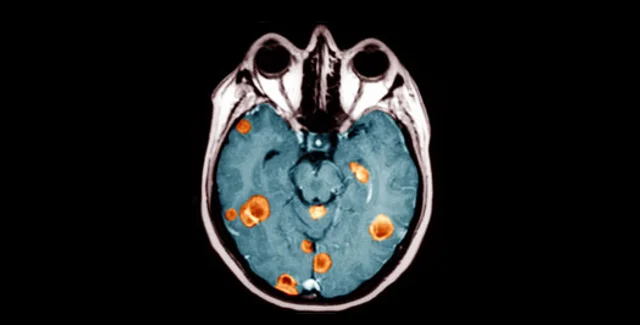

Ученые из Колумбийского университета обнаружили два гена, ответственные за возникновение одной из наиболее быстро развивающихся форм рака головного мозга

Так называемая Glioblastoma multiforme в считанные месяцы приводит к развитию неоперабельной опухоли, однако до сегодняшнего дня медики не могли понять причину столь стремительного протекания заболевания.